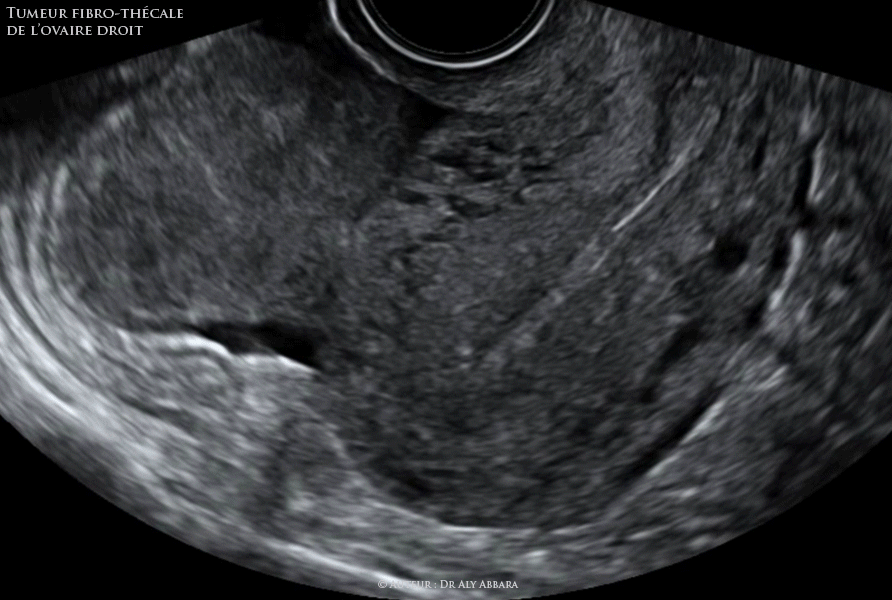

Séquences Vidéo et images échographiques mettant en évidence la présence d'une tumeur ovarienne droite, solide, mesurant 36 x 49 x 81 mm (environ 74 cm3), mobile, bien vascularisée (par l'analyse des signaux du Doppler couleur) et associée à la présence d'une ascite modérée seulement pelvienne.

Cliniquement : patiente âgée de 36 ans, mère de deux enfants, chez laquelle il a été découverte fortuitement lors d'une IRM abdomino-pelvienne, dans le cadre d'un bilan d'exploration d'une pleurésie gauche, cette masse ovarienne solide est asymptomatique. Diagnostic évoqué : syndrome de Demons-Meigs

Présence d'une ascite modérée occupant le petit pelvis.